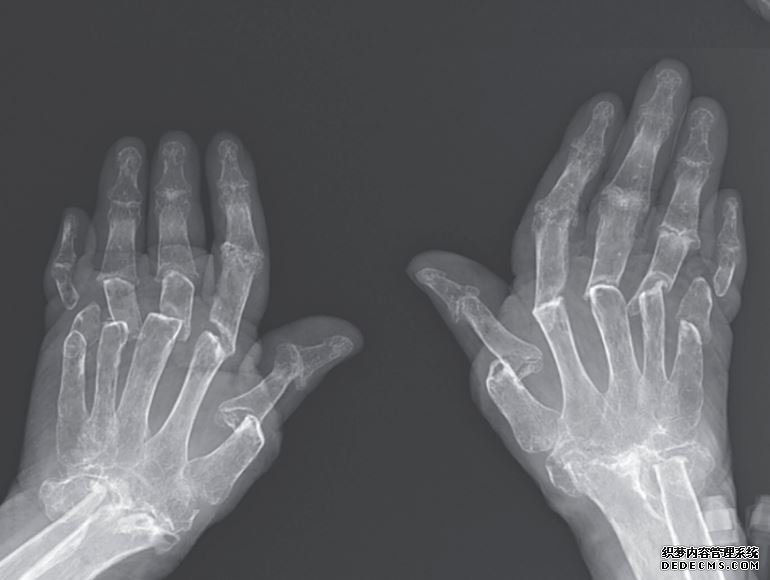

病人的手腕和手的x光片显示了损伤的程度:这位妇女的手指、手、手腕和前臂下部的骨头似乎都磨损了,好像大量的组织已经消失了。医生诊断这名妇女的手指可伸缩,医学上称为关节炎致残,并将组织损失归咎于一种叫做骨溶解的过程,这种过程会导致骨头被叫做破骨细胞的细胞“重新吸收”。

12月11日发表在《新英格兰医学杂志》(New England Journal of Medicine)上的一篇报道称,在最近的病例中,这名妇女在土耳其一家风湿病诊所接受治疗时,她的手出现了严重的畸形和肿胀。她的医生指出,这位病人18年前被诊断出患有类风湿性关节炎,随着时间的推移,她的指关节变得如此肿胀,以至于她的手指向一侧倾斜,朝向小指。在检查了病人的手之后,医生们发现她移位的手指骨似乎短得不寻常——对于这个女人来说,手指和拳头都太短了。

这位69岁的病人,由于过度活跃的破骨细胞所造成的损伤导致她的骨骼萎缩。当这个女人的手指重新合拢在手上时,她的皮肤并没有收缩到与之匹配,因此多余的组织就会皱折起来。通过轻轻地拉她的指尖,她的医生能够暂时将手指伸展到原来的长度。